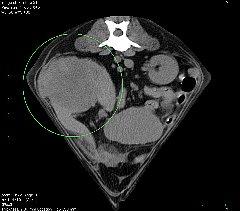

CT CT

本院では、4列マルチスライスヘリカルCT装置(TOSHIBA Asteion4)を導入しました。

1回転で4断面の画像を取得することができ,0.75秒の高速フルスキャンを可能とすることで,肺野領域30cmの範囲を最速6秒以下でスキャン可能です。

従来の1列のCTより短時間で、被爆量の少ない、正確な検査が可能です。

• 腹腔内病変

• 脾臓の血管肉腫

脾臓の血管肉腫